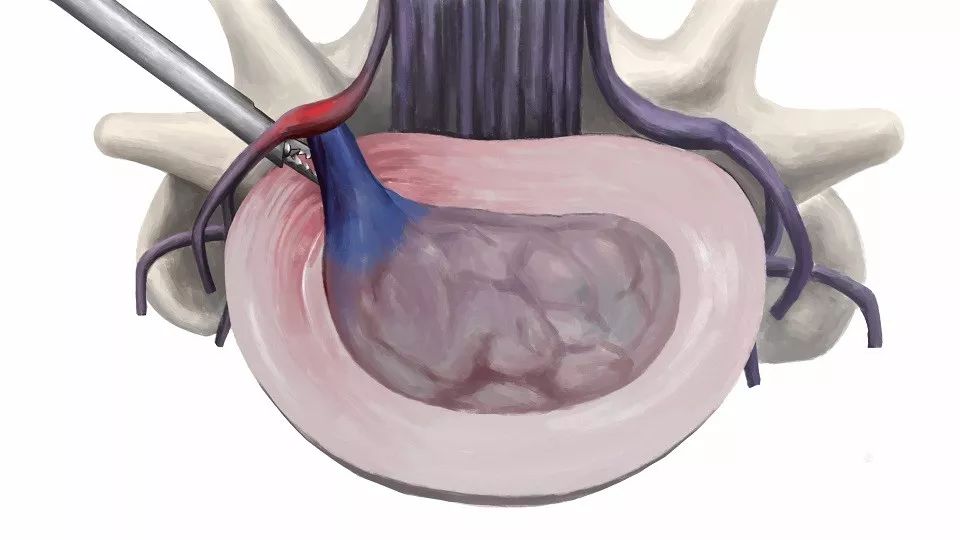

可能提到手术治疗,许多患者都会惧怕,但其实现在这方面的手术大多都是微创手术,患者术后恢复都很快。像上面这位患者的情况,常用的就是椎间孔镜技术,手术切口非常小,一般只有7mm,术后当天就能下地活动。所以,随着微创技术的发展,我们就更积极地建议那些保守治疗效果不佳、反复发作的患者早期接受手术治疗。这种患者尽早接受手术治疗,就能够更早地恢复到正常的生活或工作状态。

椎间孔镜技术属于脊柱内镜技术,近年来成熟应用于临床的尖端技术之一,秉承微创理念,脊柱稳定性影响较小。优点主要有:

1、微创:皮肤切口仅7mm;通过侧方入路到达目标区域,避免传统后路手术对椎管和神经的干扰;不咬除椎板,不破坏椎旁肌肉和韧带,对脊柱稳定性无影响。

3、安全性高:局部麻醉,患者术中全程清醒,术中能与患者互动,不伤及神经和血管;基本不出血,手术视野清晰,大大降低误操作的风险。

4、直接:直接切除突出间盘,手术减压明确。